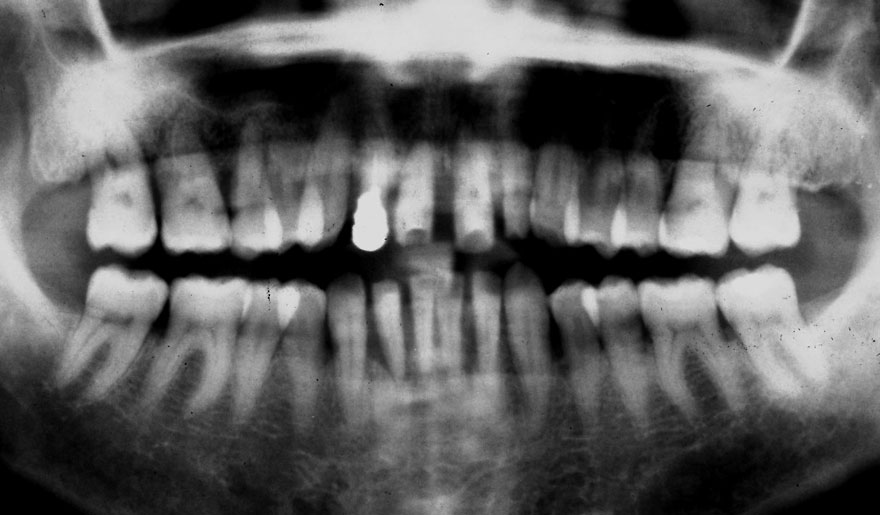

初診時 50歳 女性

河田歯科医院

30年後 80歳